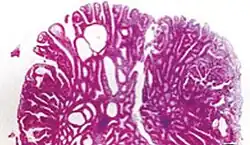

| Type | Risk of containing malignant cells | Histopathology | Image | |

| Tubular adenoma | 2% at 1.5 cm[12] | Low to high grade dysplasia[13] | Over 75% of volume has tubular appearance.[14] |

|

Adenomas

Neoplastic polyps of the bowel are often benign hence called adenomas. An adenoma is a tumor of glandular tissue, that has not (yet) gained the properties of cancer.

The common adenomas of the colon (colorectal adenoma) are the tubular, tubulovillous, villous, and sessile serrated (SSA).[18] A large majority (65–80%) are of the benign tubular type with 10–25% being tubulovillous, and villous being the most rare at 5–10%.[9]

Micrograph of a tubular adenoma, the most common type of dysplastic polyp in the colon -